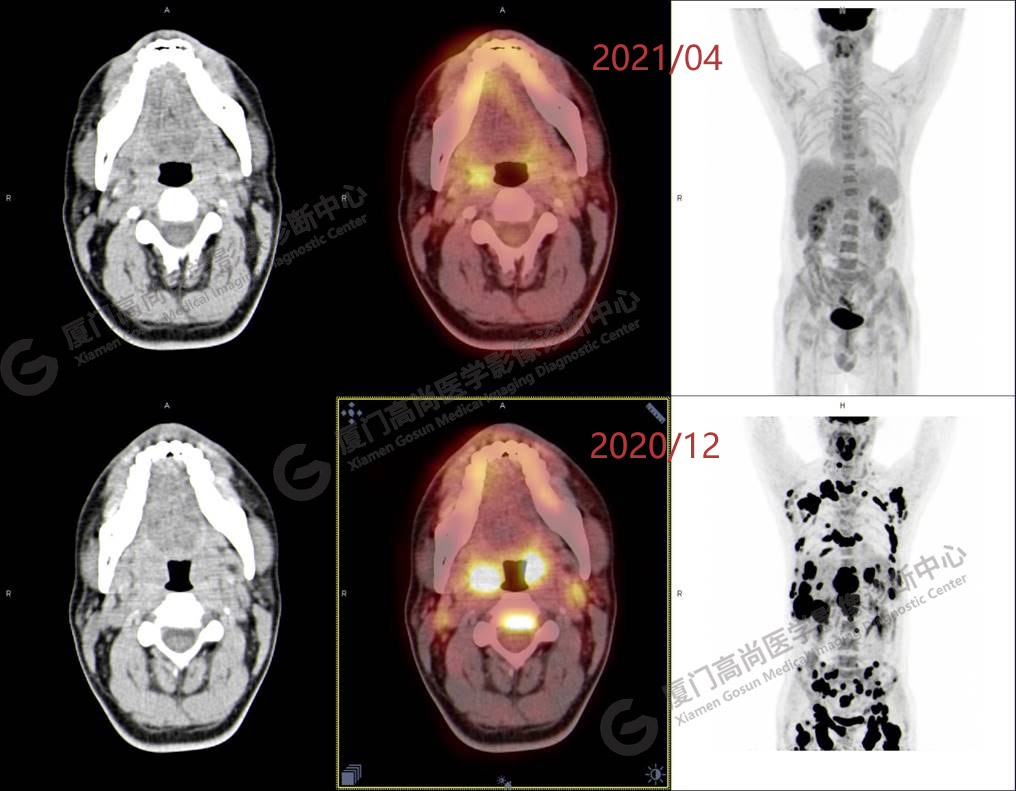

2020.12月本中心PET/CT示:全身多發(fā)腫大淋巴結(jié),代謝不同程度增高;肝臟多發(fā)稍高密度結(jié)節(jié)、脾臟多發(fā)稍低密度結(jié)節(jié),代謝異常增高;全身多發(fā)骨骼溶骨性骨質(zhì)破壞,代謝異常增高,胸2、腰1椎體病理性骨折,診斷為淋巴瘤。隨后,病理確診為彌漫大B細(xì)胞淋巴瘤。

患者化療4個(gè)療程后,于2021.04月返我中心復(fù)查,現(xiàn)患者本人已能自主行走,此次更是獨(dú)自一人來我中心復(fù)查PET/CT。檢查結(jié)果顯示:原全身多發(fā)病灶基本消失,且病灶代謝基本恢復(fù)正常。以下是患者PET/CT前后對(duì)比圖像:

PET/CT前后對(duì)比圖像2